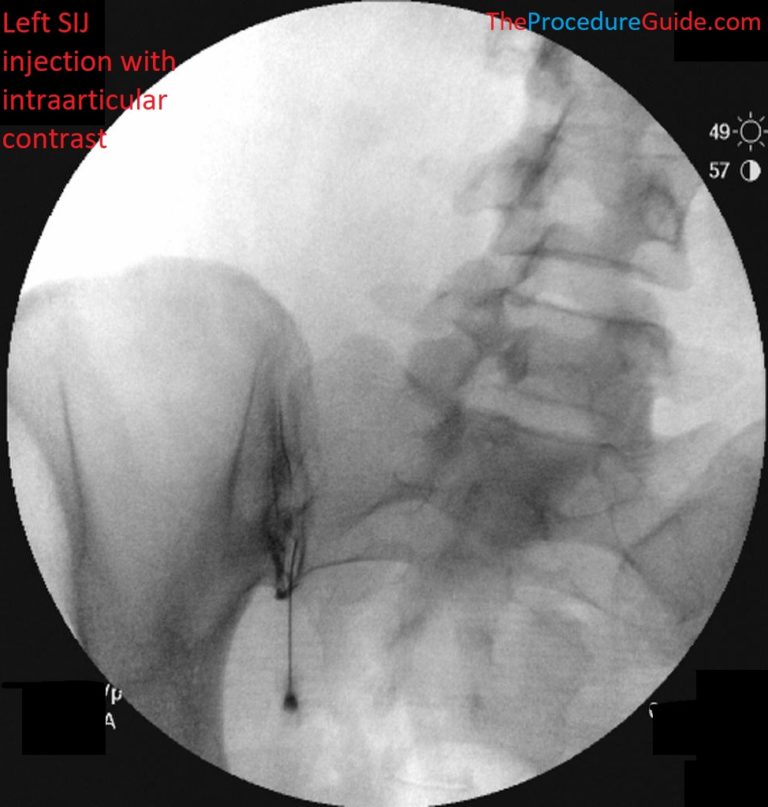

천장관절염

Fluoroscopy

기존에는 이 신경을 치료하기 위해

주로 '투시 영상 장비(Fluoroscopy)',

즉 X-ray를 이용했습니다.

뼈 구조를 보면서

신경 주변에 바늘을 접근시키는 방법이죠.

하지만 이 방법은 환자와 시술자 모두

방사선에 노출된다는 단점이 있었습니다.